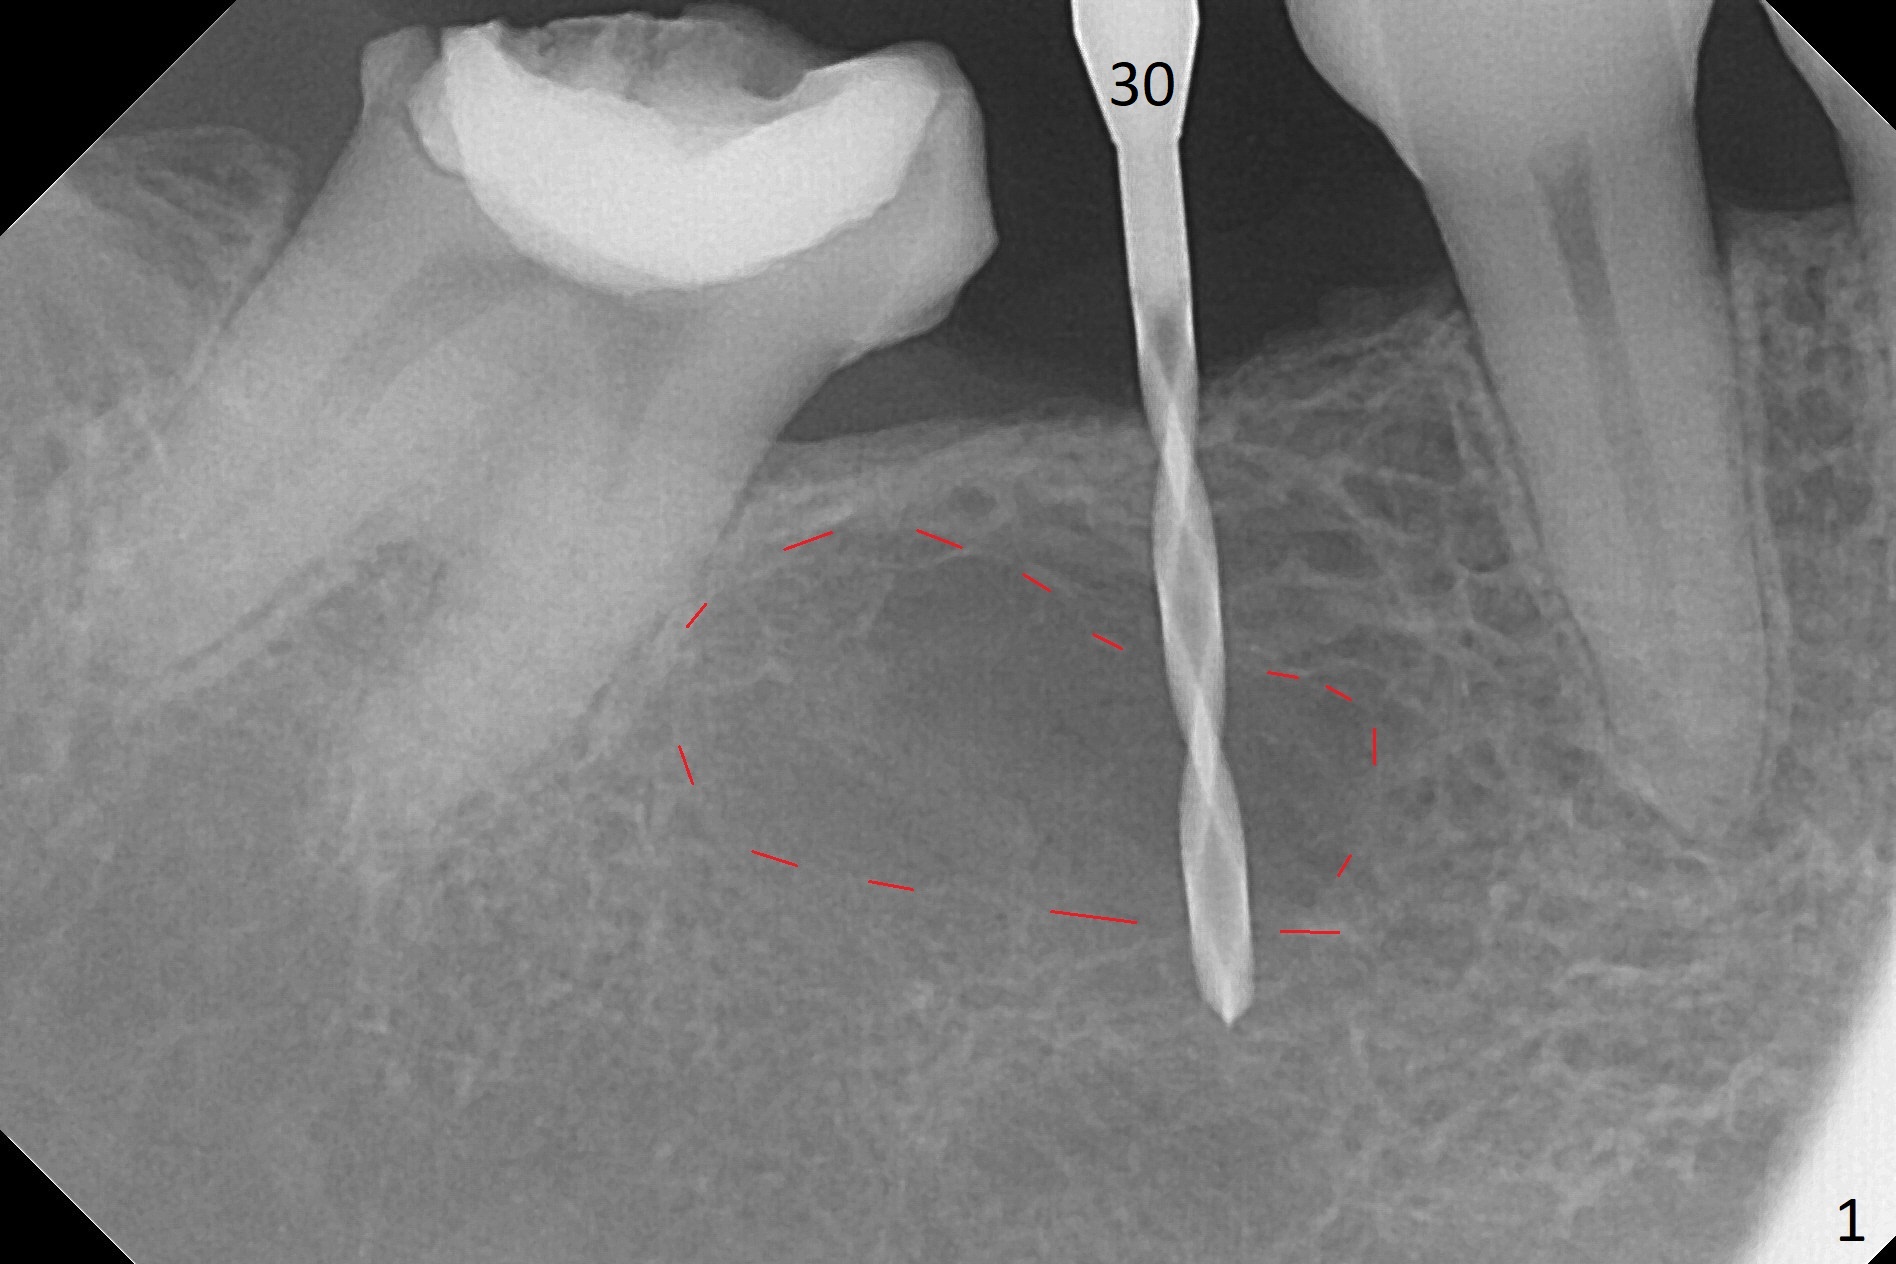

When a 1.2x12 mm drill is placed at #30, it passes the bone cavitation (Fig.1 red dashed line (low density)) twice for two-pointed fixation. So does the 3x12(2) mm 1-piece implant (Fig.2,3). The mesial margin of the tooth #31 is further reduced prior to suturing and periodontal dressing. Impression is taken 5 months postop (Fig.4). Residual cement mesial to the crown at #31 is later removed (Fig.5). Since the crowns were made at #30 and 31 at the same time, there appears no food impaction in between (Fig.6, 5.5 months post cementation).